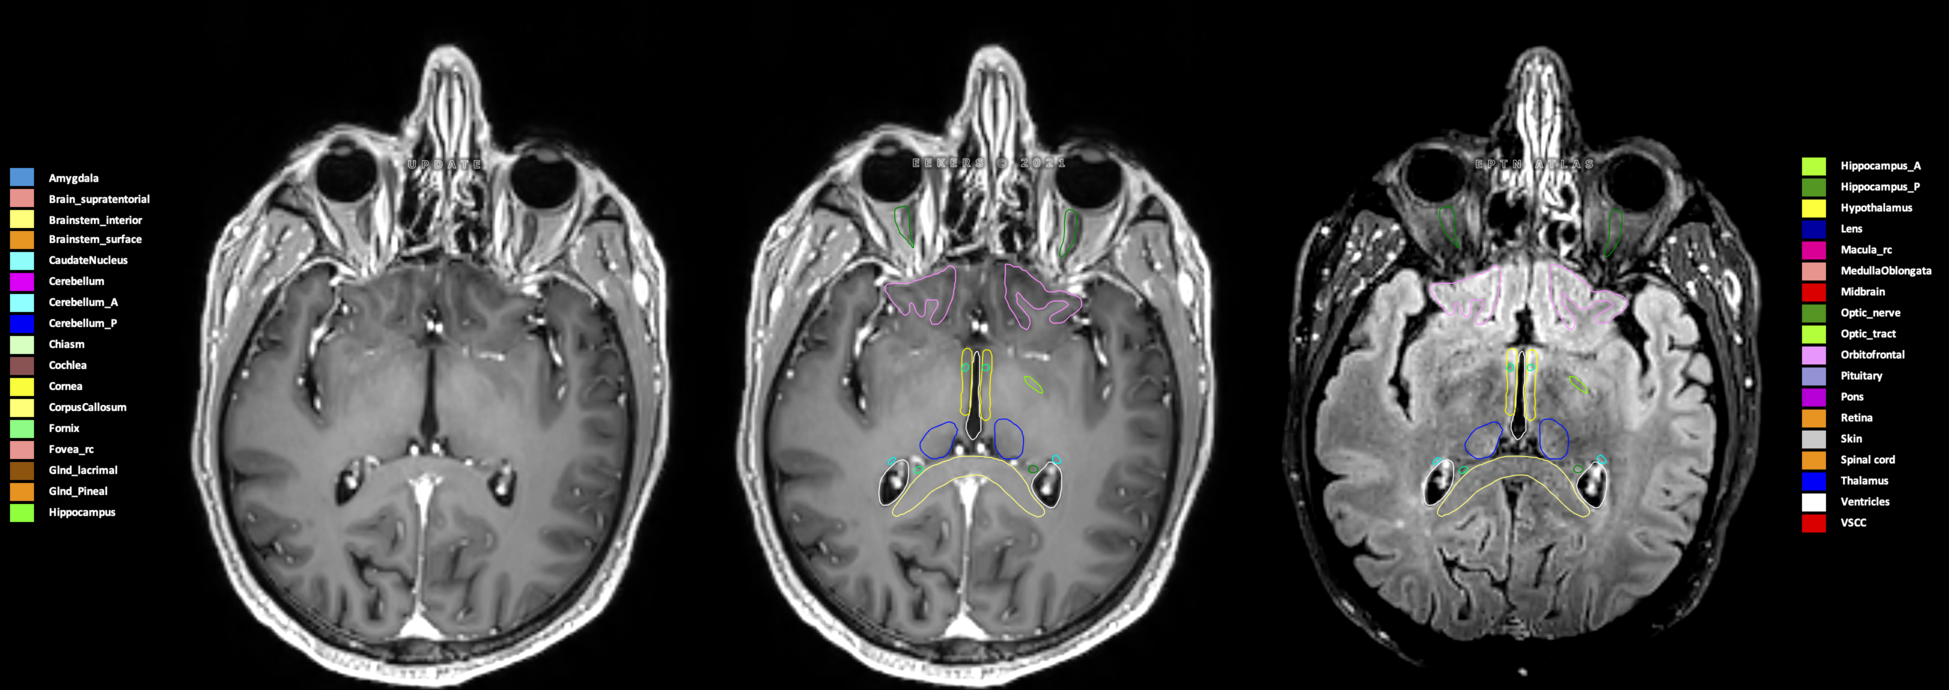

Eekers et al. have published an international neurological atlas for contouring of organs at risk in consensus with the European Particle Therapy Network (EPTN) in 2018 and an update in 2021. The purpose of this consensus atlas is to decrease inter- and intra-observer variability in delineating OARs relevant for neuro-oncology.

Included are all OARs known to be relevant for radiation-induced toxicity in neuro-oncology: brain, brainstem (midbrain, pons, medulla oblongata), chiasm, cerebellum (anterior & posterior), cochlea, cornea, hippocampus (anterior & posterior), hypothalamus, lens, lacrimal gland, optic nerve, pituitary, skin, and vestibular & semicircular canals. To further facilitate research on cognition, vision and radiological changes after irradiation of the brain, potential clinically-relevant OARs are included: amygdala, caudate nucleus, cerebellum (anterior & posterior), corpus callosum, fornix, macula, optic tract, orbitofrontal cortex, periventricular space (PVS), pineal gland, and thalamus.

Three-dimensional delineation of the 25 consensus OARs for neuro-oncology are shown on CT (WW/WL 120/40, 3000/600), 3T MR images, (T1Gd, T2FLAIR 1mm) and 7T MR (MP2RAGE 0.7 mm). All are presented in transversal, sagittal and coronal view.